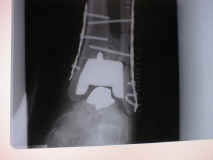

Two weeks after the surgery, the Fibula bone, which is located next to the new ankle, fractured.  After flying back to Tampa, two plates and eight screws (X-ray 1) were added.  One June 12th, 2002 the plates and screws were removed and three new screws were installed for additional support (X-ray 2).   In late 2002 Jim's third artificial ankle failed leaving Jim with few options.  Jim discovered that the University of California, San Diego had an experimental ankle transplant program.  He flew to CA and met with the two doctors who ran the program and was put on a waiting list for donor parts.  Six months later the call came and he flew to San Diego on September 21st, 2003 and had the surgery on the 22nd, receiving the ankle of a 27 year old man. After a short hospital stay he flew home to recover.

Xray2-22-01a.jpg (32146 bytes)

The old and the new. X-Ray at far right shows broken screws ready for removal

X-ray showing new metal plates and 8 screws.

The big white object is the new titanium part. The smaller part under it

is chromium cobalt steel. If you enlarge the first x-ray and look on the right side by the top corner of the titanium part, you can see the small break in the fibula.